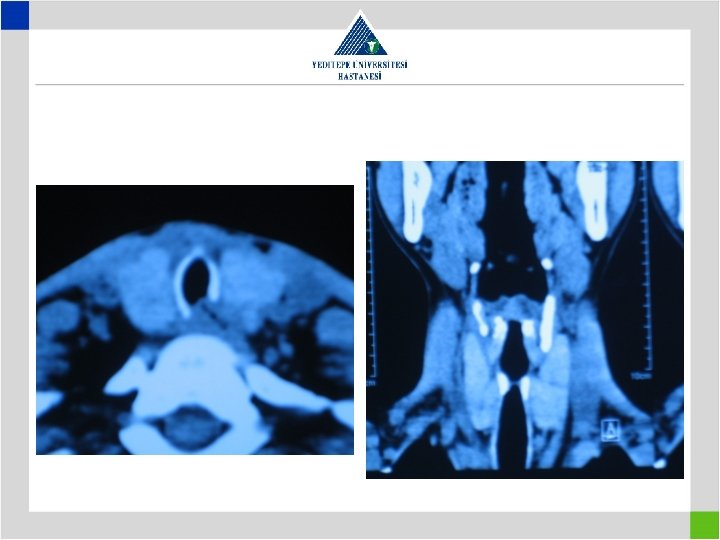

Diagnosis • Stenotic segment calculation to be correct • CT image in supine position may falsly indicate a preglottic stenosis – Overresection – increased anastomotic tension – restenosis • Pediatric trachea tolerates the tension poorly in comparison with adults – Insufficient resection – remaining fibrosis – restenosis